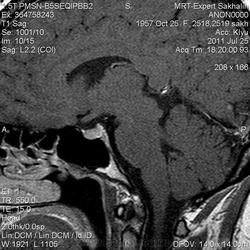

Женщина.6 лет назад выявлено образование левой доли нейрогипофиза.Пришла на контроль.

Постконтраст

Кстати, немного о внимательности-номера протоколов могут многое подсказать!